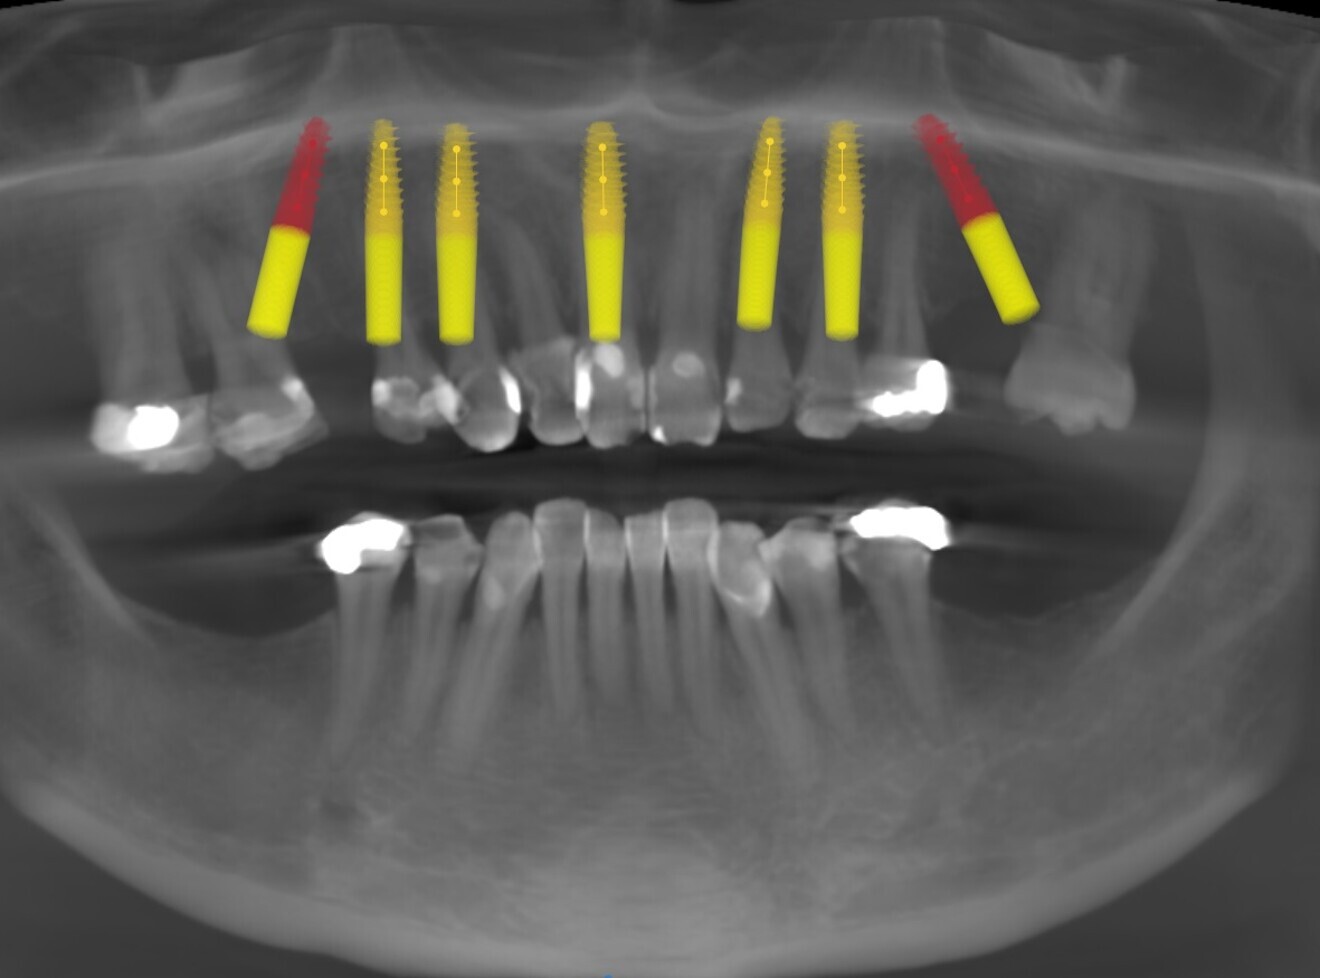

A CBCT scan and panoramic radiograph using the CS 8100 3D (Carestream Dental; Fig. 3) were taken to accurately capture the information needed to properly plan the treatment for this case that would ensure the most ideal outcome, especially since the patient had discussed how unhappy she was with her existing gummy smile. Using the CS 3D imaging software (Carestream Dental), dental implants were virtually planned in key positions to biomechanically support a full-arch fixed hybrid restoration in the maxillary arch (Fig. 4).

Fig. 3: Pre-op panoramic radiograph.

Fig. 4: Planning with the CS 8100 3D (Carestream Dental).